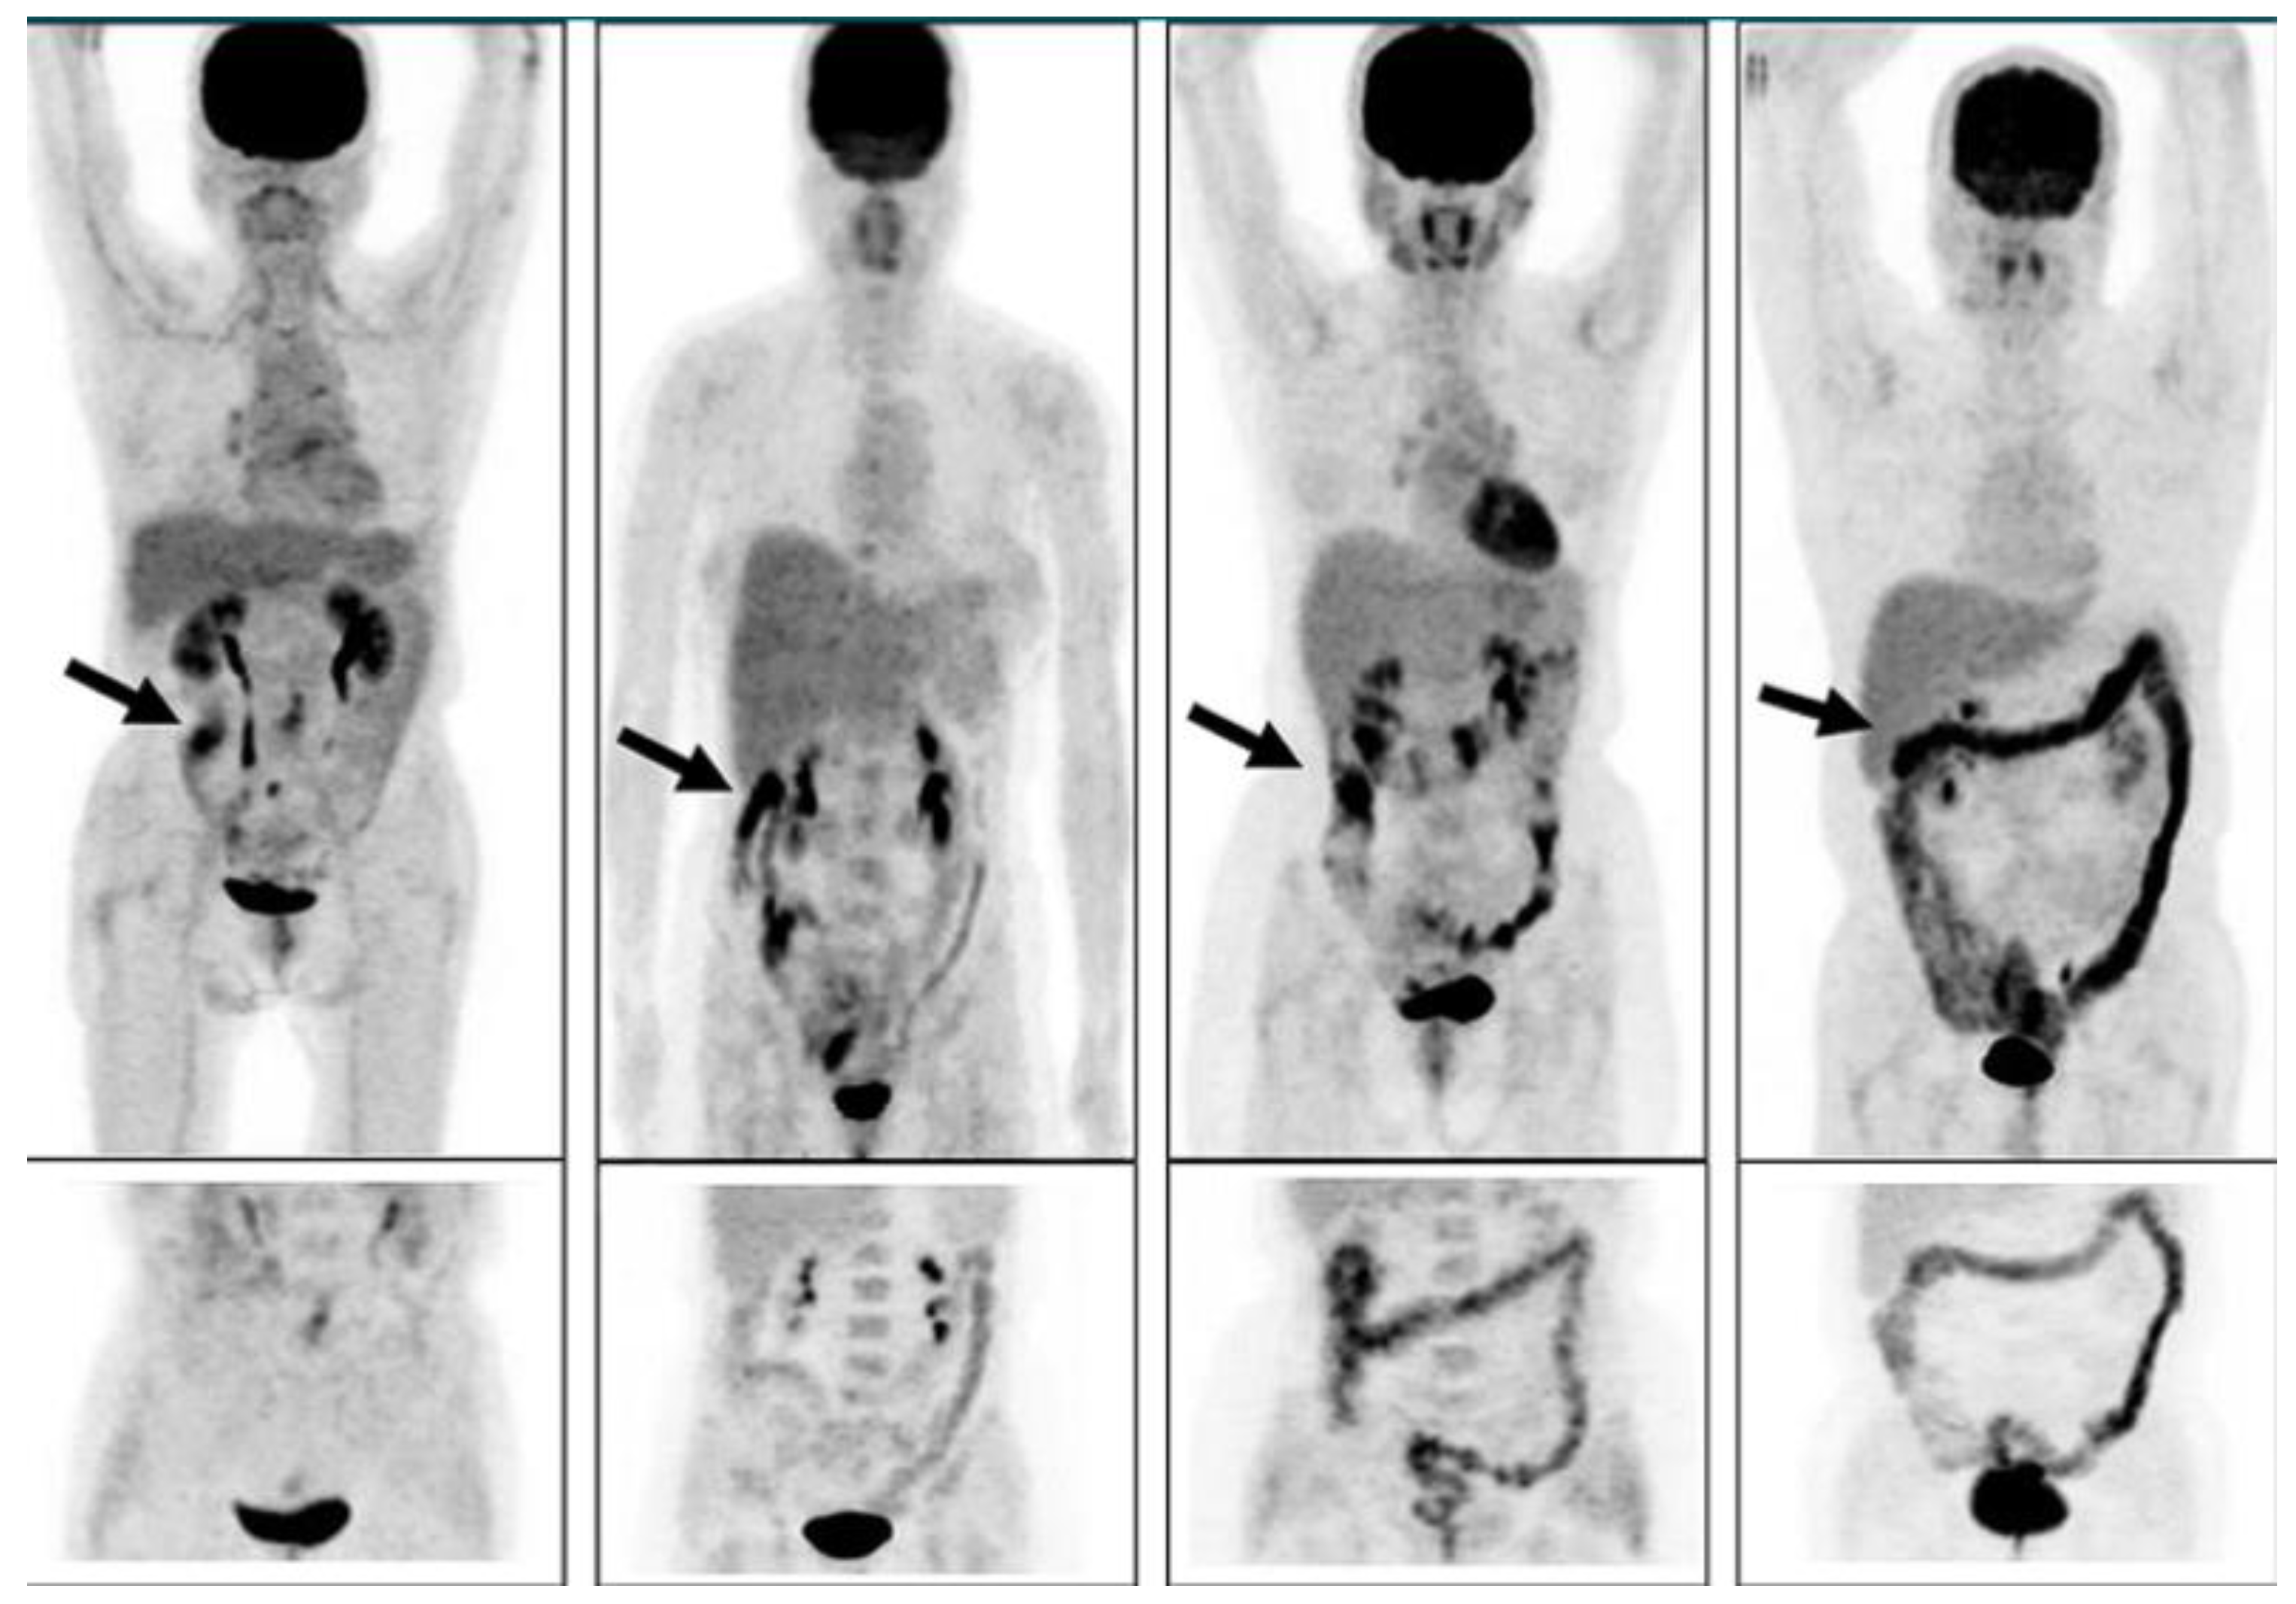

- Gontier E, Fourme E, Wartski M, Blondet C Bonardel G, Le Stanc E, Mantzarides M, Foehrenbach H, Pecking A-P, Alberini J-L.High and typical F18-FDG bowel uptake in patients treated with metformin.Eur J Med Mol Imaging 2008;35:95-99.

- Morita Y, Nogami M, Sakaguchi K, Okada Y, Hirota Y, Sugawara K, Tamori Y, Zeng F, Murokami T, Ogawa W.:Enhanced Release of Glucose Into Intraluminal Space of the Intestine Associated With Metformin Treatment as Revealed by [18F]Fluorodeoxyglucose PET-MRI.Diabetes Care 2020;43:1796-1802. [CrossRef]

- Özülkur T, Özülkur F, Mert M, Özpacaci T.Clearance of high intestinal F18-FDG uptake associated with metformin after stopping the drug.Eur J Nucl Med Mol Imaging 2010;37:1011-1017.

- Schreuder N, Klarenbeek H, Vendel BN, Jager PL, Kosterink JGW, van Puijenbroek EP.Discontinuation of metformin to prevent metformin-induced high colonic FDG uptake:is 48 h sufficient?.Annals of Neclear Medicine 2020;34:833-839.

- Massollo M, Marini C, Brignone M, Emionite B, Salani BRiondato M, Capitano S, Fitz F, Democrito A, Amaro A, Morbelli S, Piana MMaggi D, Cilli MPfeffer U, Sambuceti G.Metformin Temporal and Localized Effects on Gut Glucose Metabolism Assessed Using F18-DG PET in Mice.J Nucl Med 2013;54:259-266.

- Tu DG, Chen C-R, Wang Y-W, Tu C-W, Huang YC.Bowel-cleansing methods affecting PET-CT Image interpretation.Nucl Med Commun 2011;32:570-574.

- Chen Y-K, Chen J-H, Tsui C-C, Chou H-H, Cheng R-H, Chiu J-S.Use of Laxative-augmented Contrast Medium in the Evaluation of Colorectal Foci at FDG PET.Radiology 2011;259 (2):525-533.

- Katsumata R, Manabe N, Ayaki M, Tanikawa T, Fujita M, Ono Y, Fujiwara H, Suehiro M, Monobe Y, Kato K, Kawamoto H, Haruma K.Increased Colonic Fluorodeoxyglucose Uptake in Melanosis Coli-A Case Series of Three Patients.Gastro Hep Advances 2022;1:125-128.